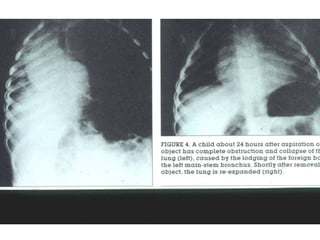

Chest X-ray forAspirated Foreign Bodies ƒ Foreign object radiopaque in 6 to 20 % ƒ CXR normal in 18 to 33 % ƒ CXR findings: –obstructive emphysema –atelectasis –pneumonia ƒ Expiratory film enhances CXR yield

Left X-ray showsair trapping ; right X-ray (different patient) shows atelectasis